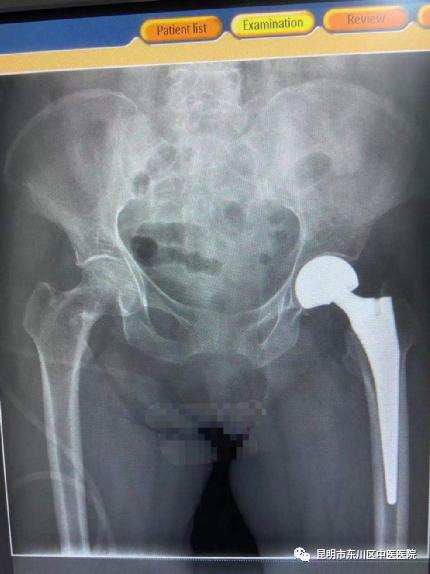

9月30日,东川区中医医院骨科团队在杨红俊副院长带领下,历时1小时,顺利完成了首例髋关节置换手术。

患者文女士,75岁,于2021年9月27日在家中不慎受伤,门诊以“左股骨颈骨折”收治住院。经精心的术前准备,于9月30日行腰硬联合麻醉下行“左股骨颈骨折人工髋关节置换术”,术后患者生命征平稳,感觉良好。

此次手术,是东川区中医医院“基层综合服务能力提升”和“骨伤科省级重点专科”创建的一个成效体现,是医院首例不依靠上级专家指导自主完成的手术,标志着医院关节外科取得重大突破。